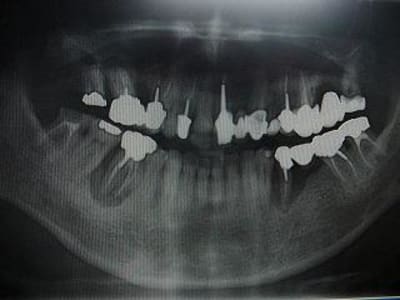

voici un cas paro qui me pose problème: Homme 39 ans, non fumeur, exellente santé ( spotif +++). PAJ dans un mauvais contexte occlusal ( bout à bout et contact essentiellement en posterieur. Je suis un peu paumé sur ce coup là! surtout sur le devenir des molaires. Des pistes avant d'en parler à nice? merci

ci joint des retro de mars 2001 et aout 2003 de 46 qui montre l'evolution du cas..

Je ne suis pas sûr de voir une PAJ avec les destructions dentaires visibles à la pano.

D'autant que sur tes rétro la lésion évolue autour d'une dent, la 46, de façon évidente alors que 47 n'a pas bougé.

Le problème est évidemment d'origine endodontique sur ces deux dents. Regarde les lésions. Cette guangue autour de 46 et 35 (si ma memeoire est bonne ) est caractéristique.